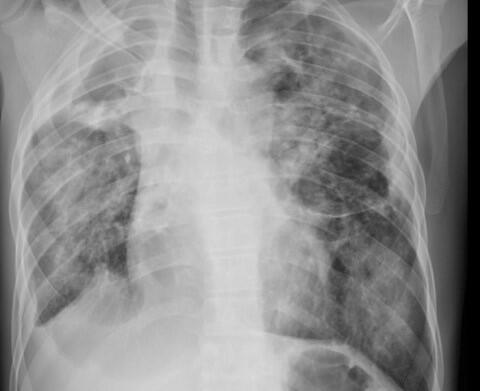

Most of these patients had more than one condition that cause breathlessness, including pneumonia, anaemia, heart failure and TB.

Of these patients, 69% who had heart failure had died within a year, alongside 57% with anaemia, 53% with pneumonia, and 47% with TB. Most patients (63%) had multiple conditions, a factor associated with increased mortality.